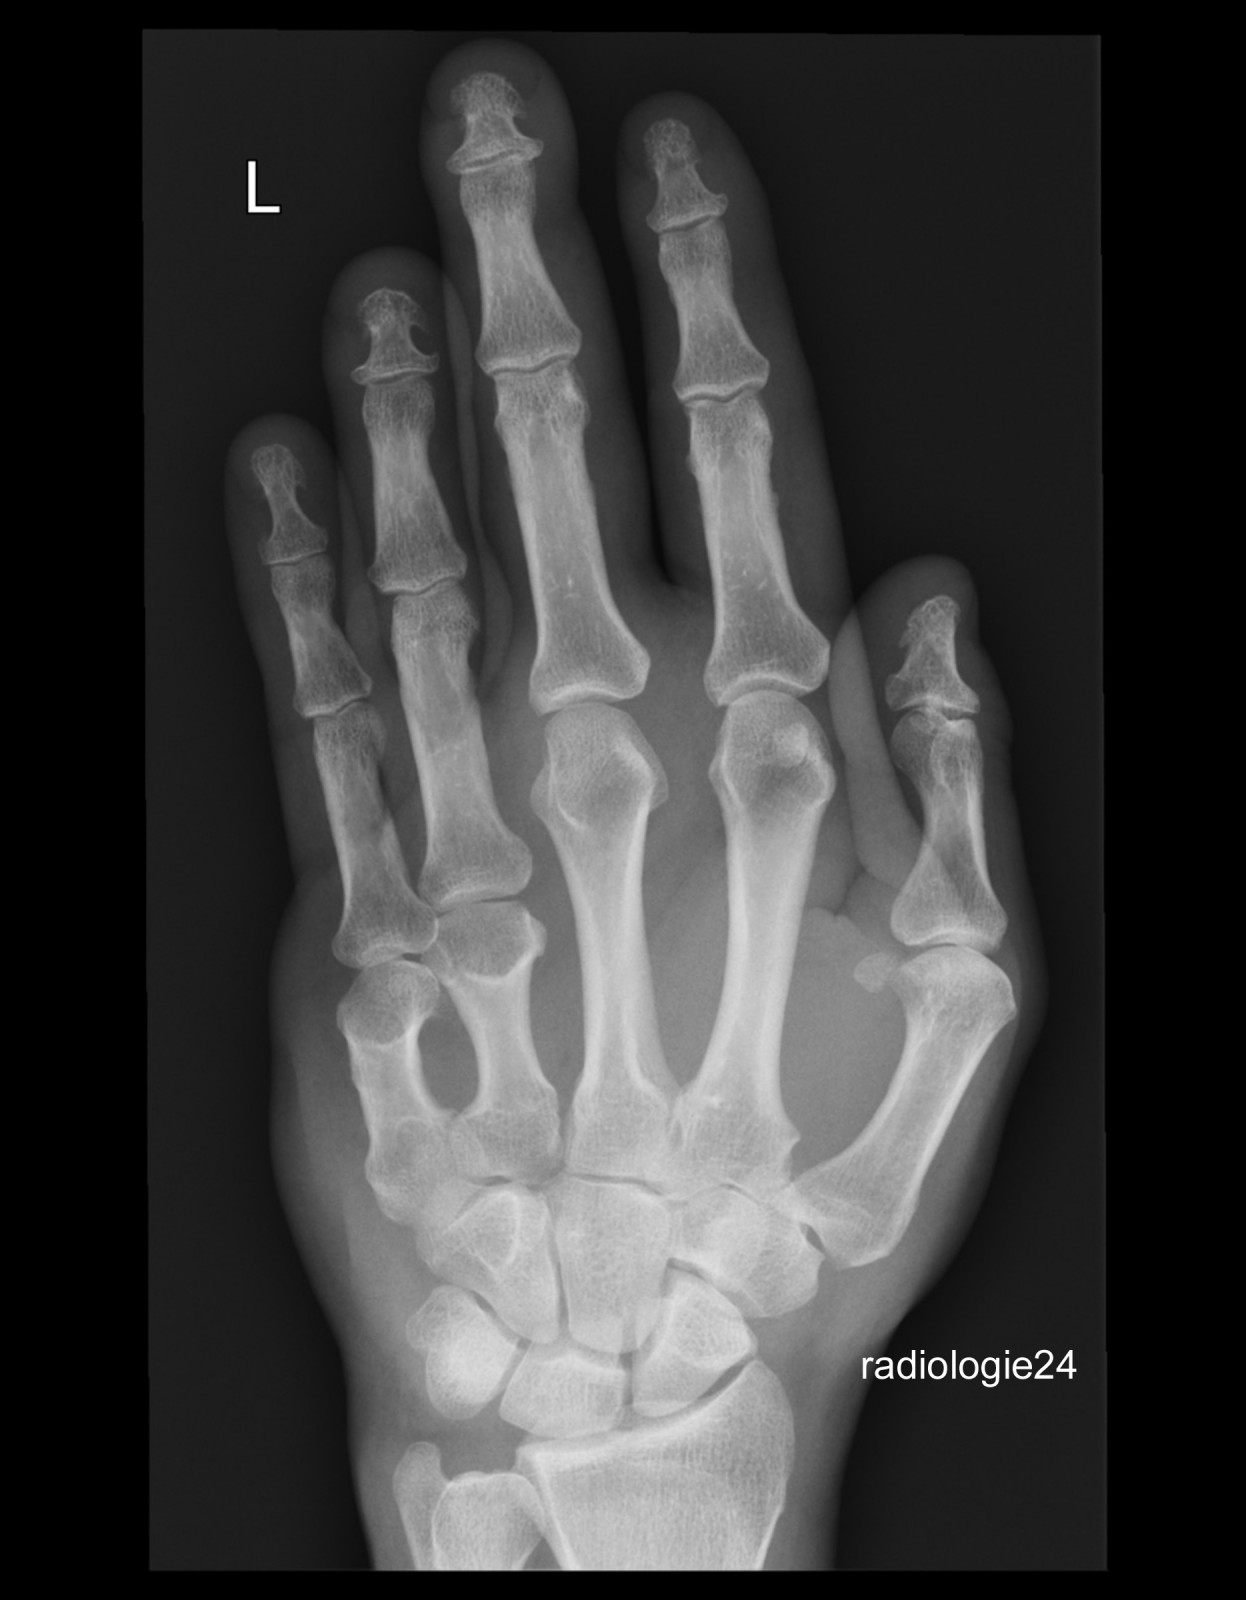

Röntgenfall des Monats Juni 2018 mit Auflösung

45 jähriger Patient Z.n. Sturz. Schmerzen Metacarpalia II/III. Fraktur? Ihre Diagnose?

Bild vergrössern

Link zur Auflösung mit ausführlichem Befund:

https://www.radiologie24.ch/radiologie-mediathek/roentgenfall_des_monats